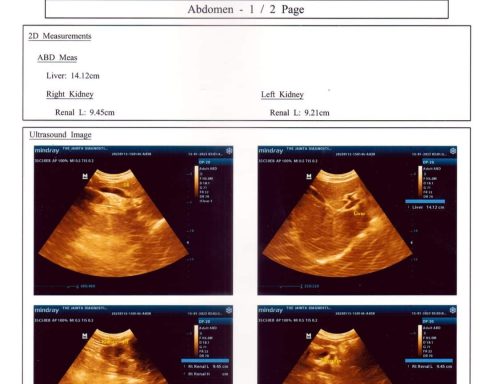

হাড়ভাঙার চিকিৎসা নিতে গিয়ে ডাক্তারা চুরি করল কিডনি, আদালতে মামলার আবেদন সিলেটের এম এ জি ওসমানী মেডিকেল কলেজ হাসপাতালে হাতের হাড় ভাঙার চিকিৎসা নিতে গিয়ে অস্ত্রোপচারের মাধ্যমে এক ব্যক্তির (কিডনি চুরি) অপসারণ…